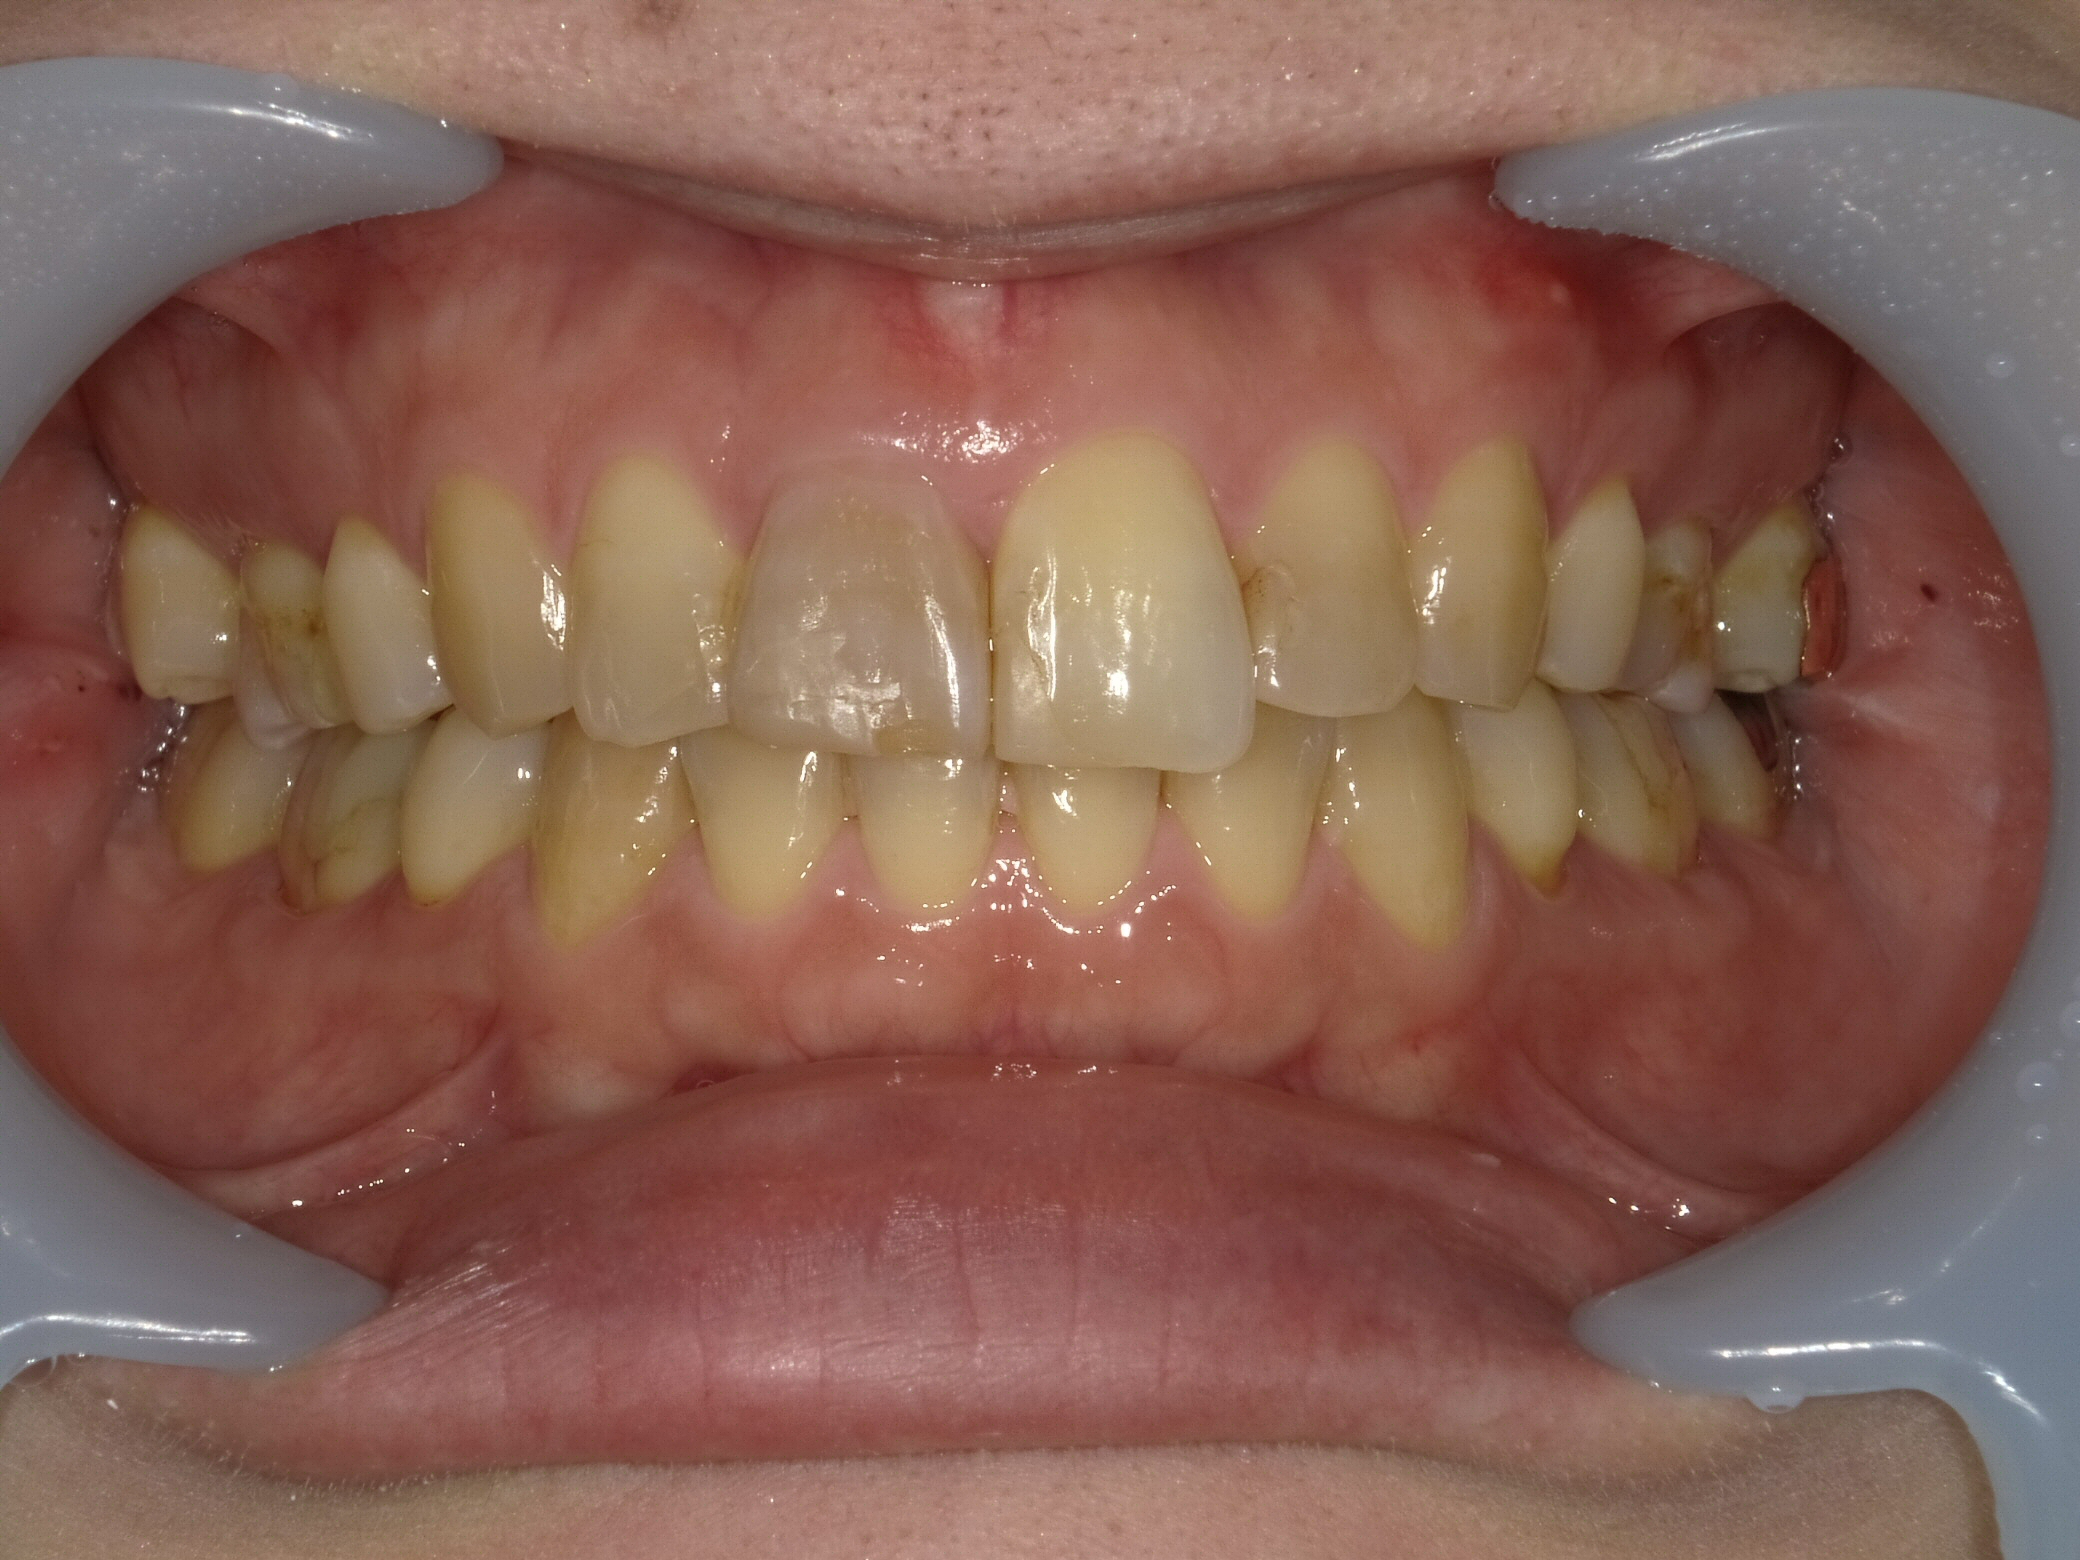

症例1:神経のない歯の変色を改善

「1本だけ色が暗く、笑うときに気になる」というケースです。周りの天然歯に完全に調和させることを目指しました。

【Before】(矢印が神経のない変色歯)全体をホワイトニングしてベースを明るくします。